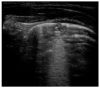

The potential role of ultrasound for the diagnosis of pulmonary diseases is a recent field of research, because, traditionally, lungs have been considered unsuitable for ultrasonography for the high presence of air and thoracic cage that prevent a clear evaluation of the organ. The peculiar anatomy of the pediatric chest favors the use of lung ultrasound (LUS) for the diagnosis of respiratory conditions through the interpretation of artefacts generated at the pleural surface, correlating them to disease-specific patterns. Recent studies demonstrate that LUS can be a valid alternative to chest X-rays for the diagnosis of pulmonary diseases, especially in children to avoid excessive exposure to ionizing radiations. This review focuses on the description of normal and abnormal findings during LUS of the most common pediatric pathologies. Current literature demonstrates usefulness of LUS that may become a fundamental tool for the whole spectrum of lung pathologies to guide both diagnostic and therapeutic decisions.